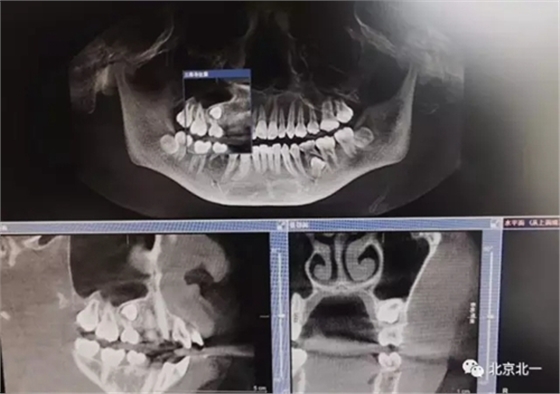

圖一:拔牙前影像片(CBCT)

術(shù)后拍片